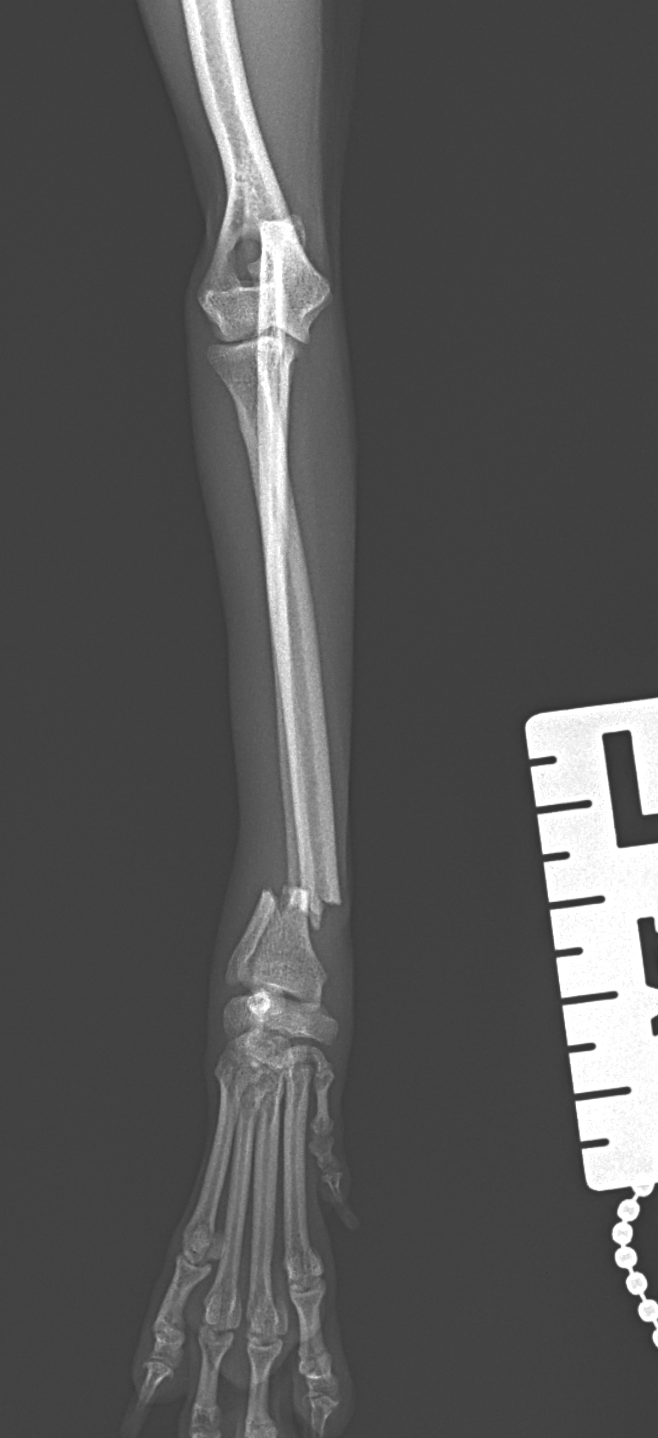

橈骨固定術 #270 極小犬(1.4kg)の橈骨固定術依頼です。骨幅3.8mmに対して1.2 Titanium Locking Plateと自家海綿骨移植を実施しています。初期固定強度を担保するために、外固定を併用しながらしばらくは安静が必要です。 症例カテゴリー 放射線治療整形外科軟部組織外科脳神経外科内科腫瘍外科救急・集中治療リハビリテーション科腫瘍内科内視鏡科脳神経科呼吸器外科中医・漢方猫の腎移植循環器科